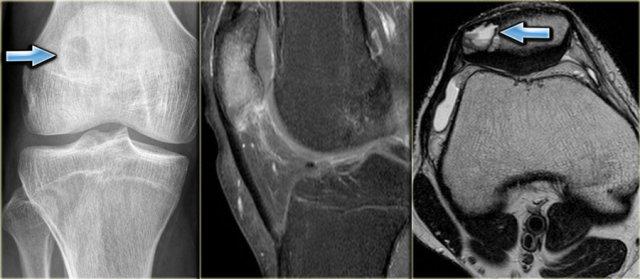

Chondroblastoma

Xương bánh chè, xương cổ tay và xương cổ chân có thể được xem như là đầu xương trong chẩn đoán phân biệt.

Bên trái là hình ảnh u nguyên bào sụn nằm ở xương bánh chè.

Discriminators :

- must be under age 30.

- must be in the epiphysis.